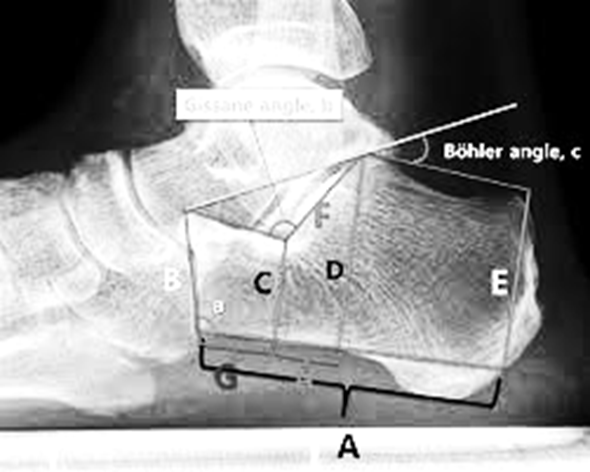

Böhler’s Angle is measured on a lateral X-ray and represents the angle formed between two lines drawn across specific landmarks of the calcaneus:

1. The first line connects the highest point of the calcaneal tuberosity to the highest point of the posterior facet.

2. The second line extends from the highest point of the posterior facet to the anterior process of the calcaneus.

The angle formed between these two lines is referred to as Böhler’s angle.

📏 Normal Range:

Böhler’s angle typically falls within the normal range of 20° to 40°.

An angle less than 20° is suggestive of a calcaneal fracture.

🩺 Clinical Significance:

• A decreased Böhler’s angle indicates depression or collapse of the calcaneus, which helps assess the severity of the fracture.

• Restoring this angle postoperatively is one of the primary goals of treatment.